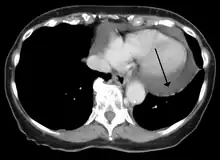

Echocardiogram (ultrasound): when pericardial effusion is suspected, echocardiography usually confirms the diagnosis and allows assessment of the size, location and signs of hemodynamic instability.[4] A transthoracic echocardiogram (TTE) is usually sufficient to evaluate pericardial effusion and it may also help distinguish pericardial effusion from pleural effusion and MI. Most pericardial effusions appear as an anechoic area (black or without an echo) between the visceral and the parietal membrane.[1] Complex or malignant effusions are more heterogeneous in appearance, meaning they may have variations in echo on ultrasound.[5] TTE can also differentiate pericardial effusion based on the size. Although it's difficult to define size classifications because they vary with institutions, most commonly they are as follows: small <10, moderate 10–20, large >20.[5] An echocardiogram is urgently needed for evaluation when there is concern for hemodynamic compromise, a rapidly developing effusion or history of recent cardiac surgery/procedures.[1]

Cardiac CT and MRI scans: cross-sectional imaging with computed tomography (CT) can help localize and quantify the effusion, especially in a loculated effusion (an effusion contained to one area).[12] CT imaging also helps assess for pericardial pathology (pericardial thickening, constrictive pericarditis, malignancy-associated pericarditis).[1] Whereas cardiac MRI is reserved for patients with poor echocardiogram findings and for assessing pericardial inflammation, especially for patients with continued inflammation despite treatment.[5] CT and MRI imaging can also be used for continued follow up on patients.